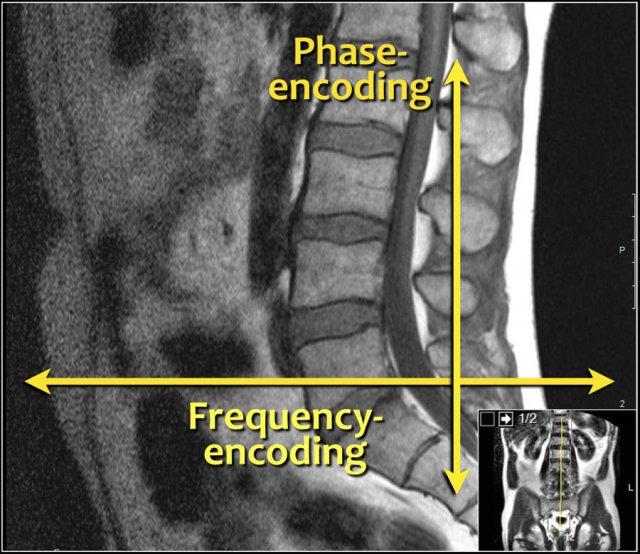

Hướng mã hóa tần số nên đặt theo chiều trước-sau (AP) và do đó hướng mã hóa pha sẽ theo chiều chân-đầu.

Cách thiết lập này có một số ưu điểm:

- Độ phân giải cao nhất theo hướng mã hóa tần số.

Chúng ta cần độ phân giải cao nhất theo chiều trước-sau để phát hiện các thoát vị nhỏ và xác định rõ ranh giới các rễ thần kinh. - Khi đặt mã hóa pha theo chiều trước-sau, sẽ xuất hiện xảo ảnh do chuyển động hô hấp. Đó là lý do một số người sử dụng dải bão hòa hoặc RFOV.

Khi đặt mã hóa tần số theo chiều trước-sau, các vấn đề này sẽ không xảy ra và không cần sử dụng dải bão hòa. - Mã hóa tần số theo chiều chân-đầu có thể dẫn đến hiển thị kém các mâm đốt sống do xảo ảnh dịch chuyển hóa học tại vị trí tiếp giáp giữa mỡ trong thân đốt sống và nước trong đĩa đệm.

Đây là lý do thêm để sử dụng mã hóa pha theo chiều chân-đầu và mã hóa tần số theo chiều trước-sau.